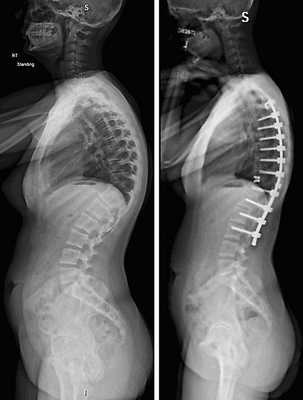

| Транспедикулярная инструментация кифоза | 120000-165000 |

Коррекция кифоза грудного отдела.